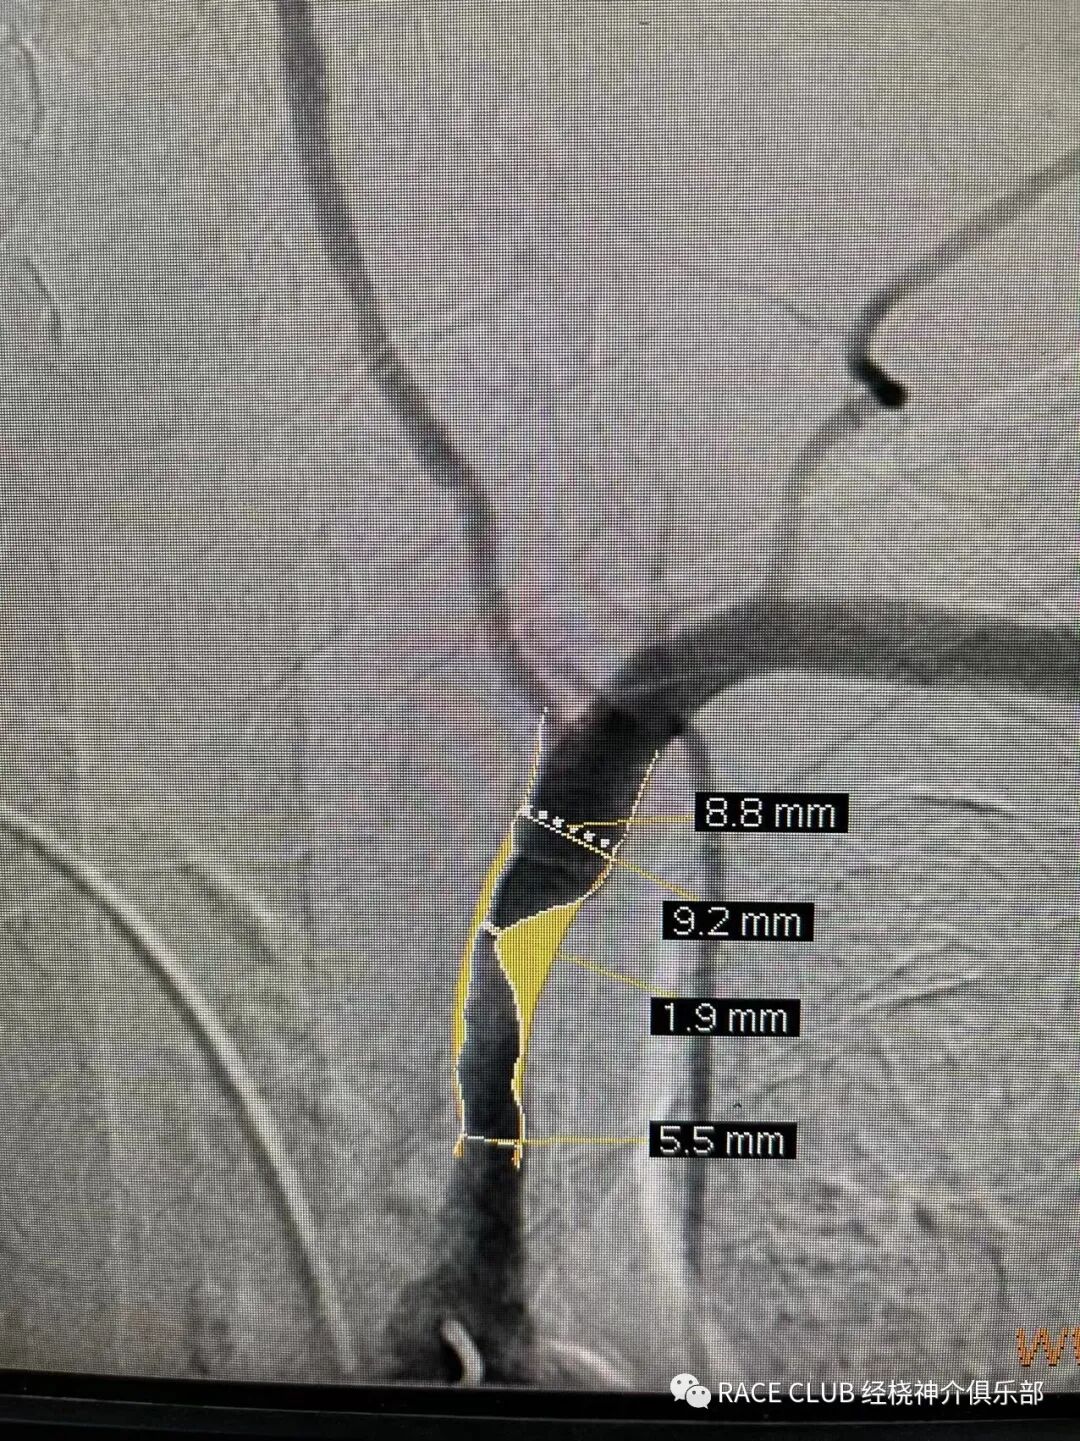

我桡上过6fGuiding做颈

6f椎动脉通过没问题

颈动脉8mm以下

@郭医生 是的,7以下pc和8以下的wallsent

6f导引导管可以走7mm的wallstent

6F进7wallstent、8及以下的precise没问题,我用过的锥形支架都不行(目前我们用的几款都不行)

protege所有的都不行,好像只有pc和wasent